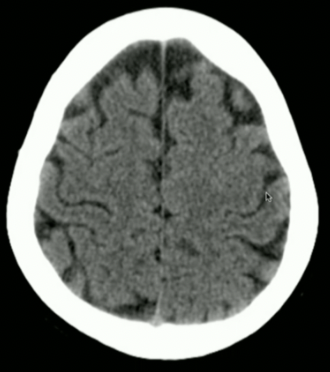

<p>Locate: Sulci, Grey Matter + White Matter</p>

Locate: Sulci, Grey Matter + White Matter